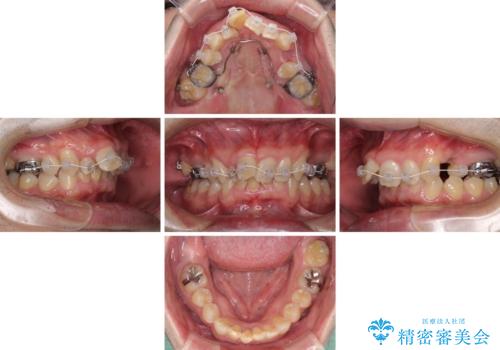

上顎歯列の叢生が著しかったため、上顎左右第一小臼歯2本を抜歯し、目立たないワイヤー装置にて治療を進めることとしました。

矯正治療後にはオーダーメイドタイプのオールセラミッククラウンを装着し、自然な口元に仕上がりました。